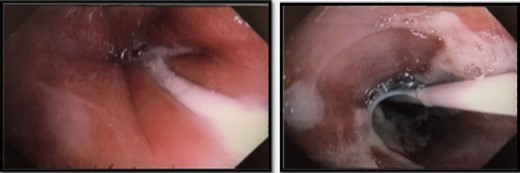

He was kept nil orally. Analgesia, antiemetics, IV proton pump inhibitor, and empirical IV antibiotics were commenced. Esophagastroscopy showed large hiatus hernia with reflux esophagitis. Middle-lower third esophagus appeared patchy, gangrenous from 27 cm to gastroesophageal-junction at 35 cm (Fig. 2). Multiple biopsies for viral culture and microbiology showed chronically inflamed cell infiltrates consistent with mucosal ischemia. No viral inclusions are seen. At the end of procedure, a PEG with jejunal extension tube was inserted to commence feeds.